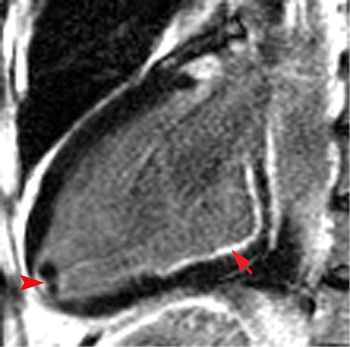

This delayed enhanced IR image shows two small thombi at the apex of the left ventricle adjacent to an apical infarct (arrowhead). They do not take up any contrast agent, which is typical of intracardiac thrombi. Also note the basal inferior wall subendocardial DHE consistent with subendocardial infarction (arrow).